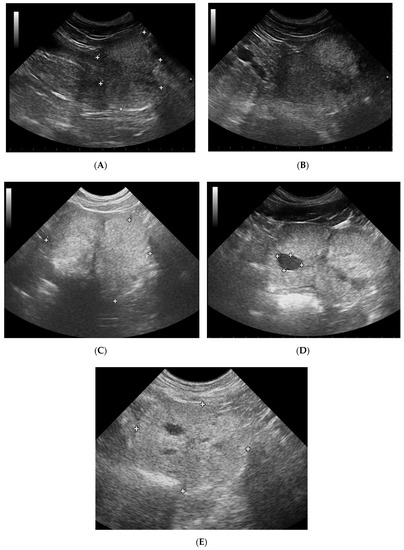

2.3. B-Mode Ultrasonography—Prostate Gland

3.1. Prostate B-Mode Appearance